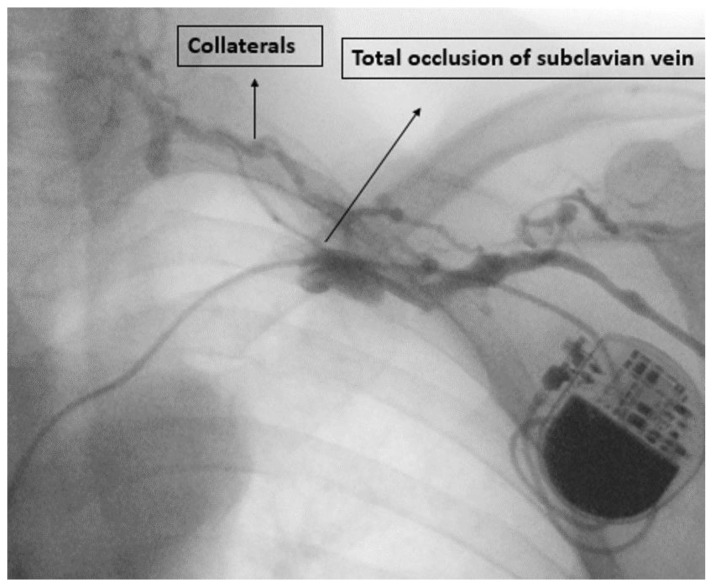

Methods: This study was a single-center prospective, observational study. Demographic, clinical, procedural, and device data was collected. All patients underwent a preimplant contrast and repeated venography at twelve months to look for upper limb venous anatomy, obstruction, or collaterals.

Abstract Image